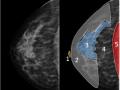

Bases físicas da mamografia